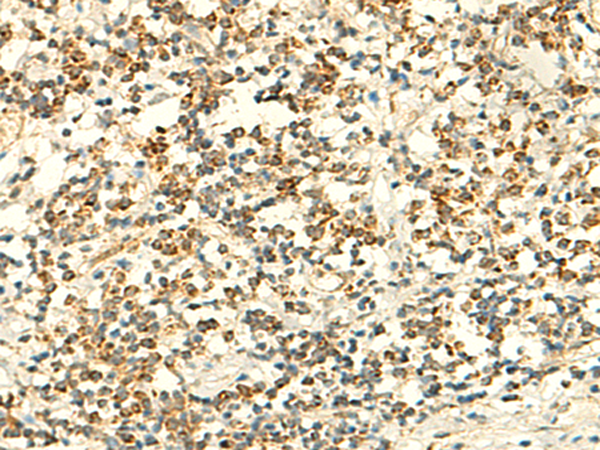

IHC positive control: |

Human tonsil and Human colorectal cancer |

IHC Recommend dilution: |

50-300 |